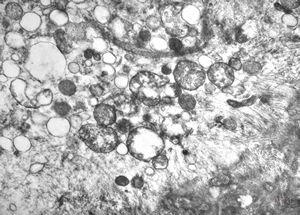

F,46y. | myopathy - steatosis

M,61y. | myopathy - steatosis

F,32y. | muscular dystrophy - steatosis